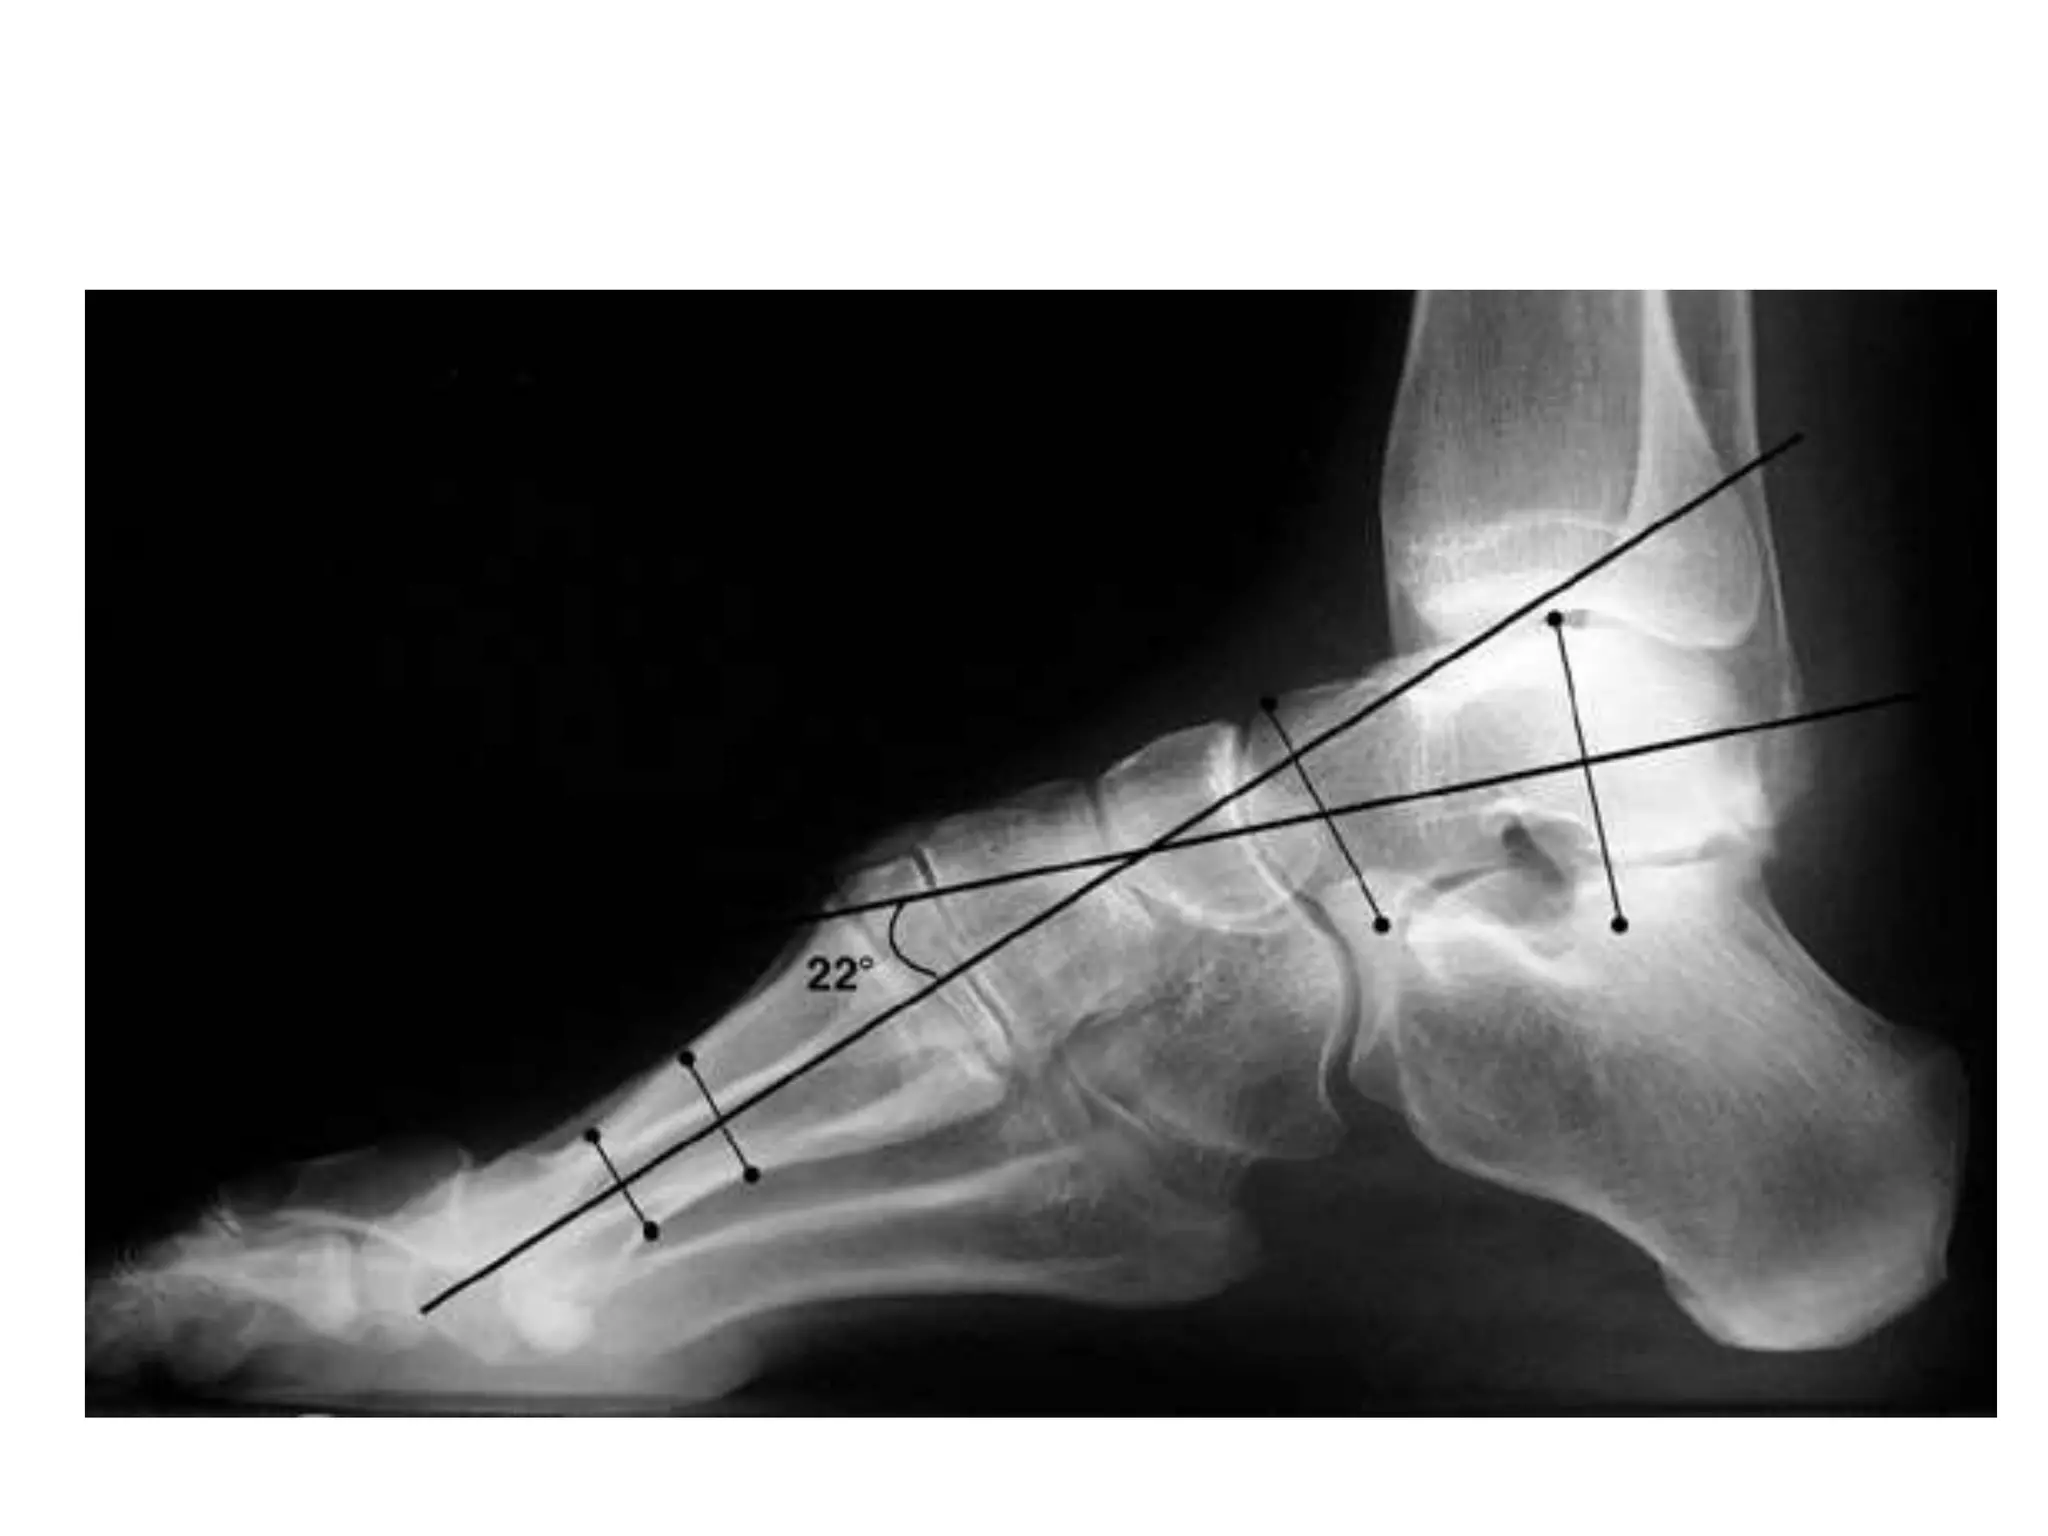

Meary angle

• B/n long axis of the talus and the long axis of

the 1st MT

• Normally, these lines are colinear

• apex directed dorsally-cavus foot

• apex angled plantarward- valgus or flatfeet

Meary angle • B/nlong axis of the talus and the long axis of the 1st MT • Normally, these lines are colinear • apex directed dorsally-cavus foot • apex angled plantarward- valgus or flatfeet